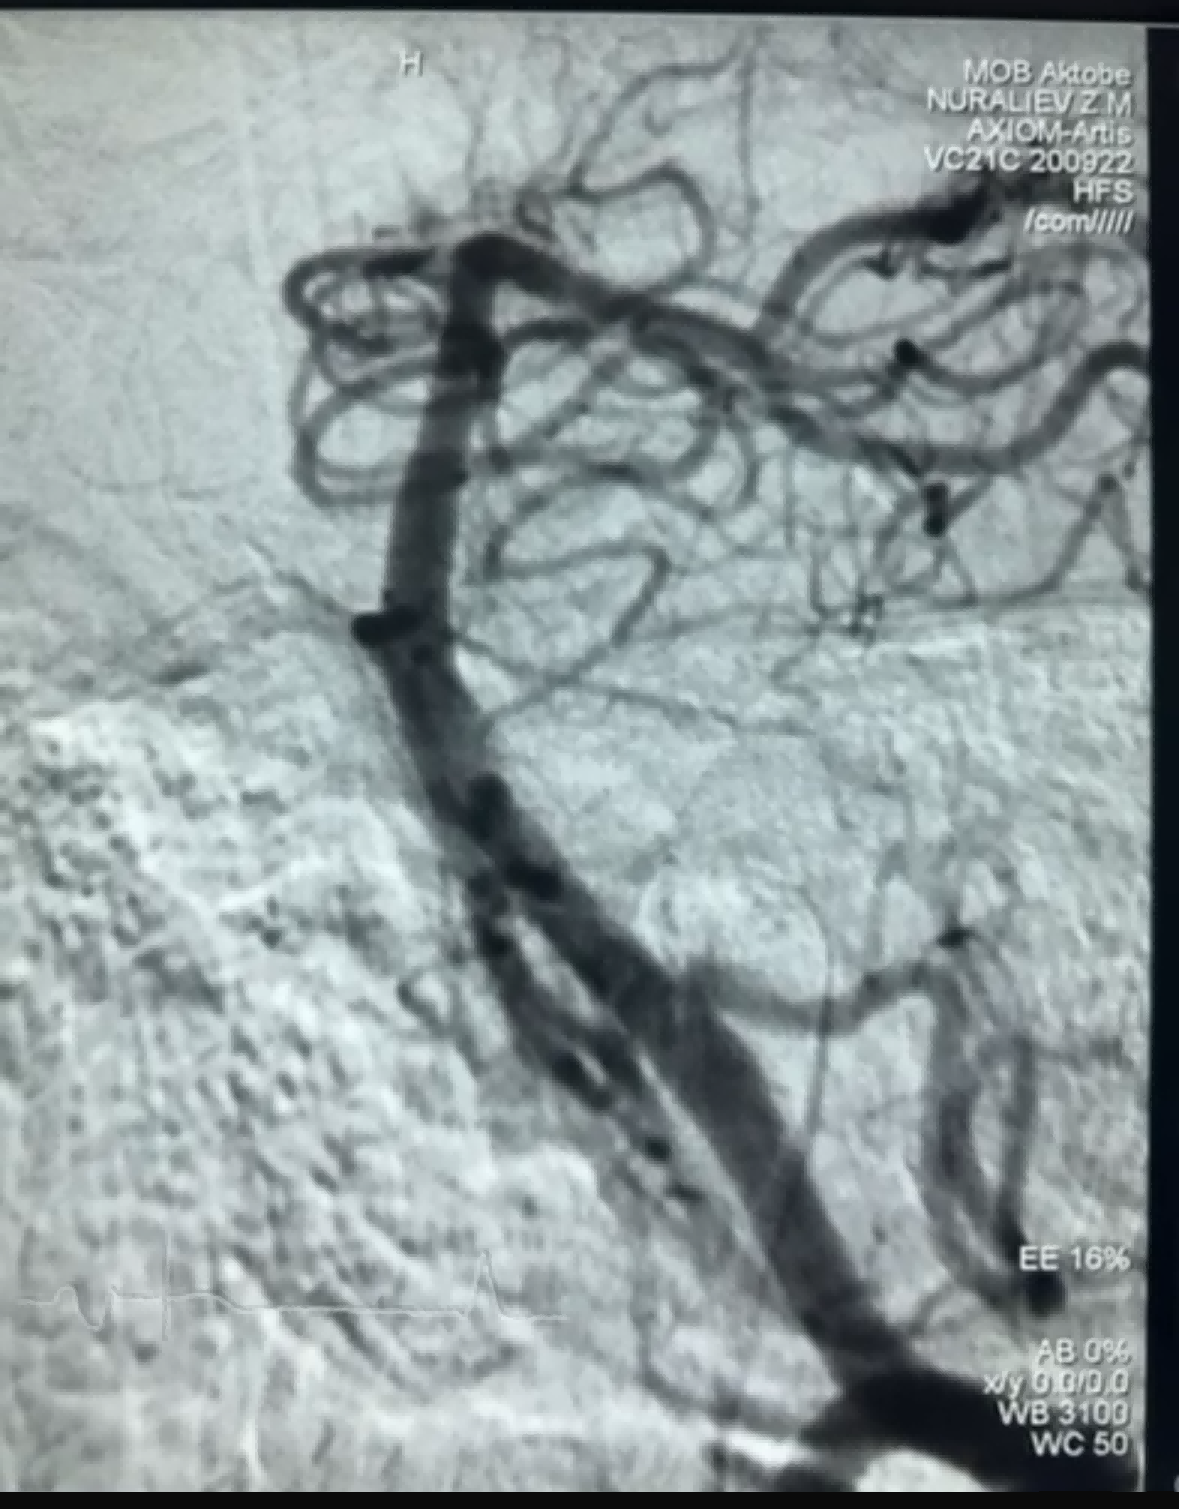

Dènyèman, te gen yon ka thrombectomy siksè lè l sèvi avèk Dredger Stent Retriever nan NeuroSafe Medical Co., Ltd. Dredger Stent Retriever a gen yon pwent mou ki pa pwogrese, ki redwi anpil risk pou domaj entim, e li gen yon twou inik ki gen fòm espesyal. konsepsyon ki kaptire boul nan san sitou pa blocage chanjman diferans yo.